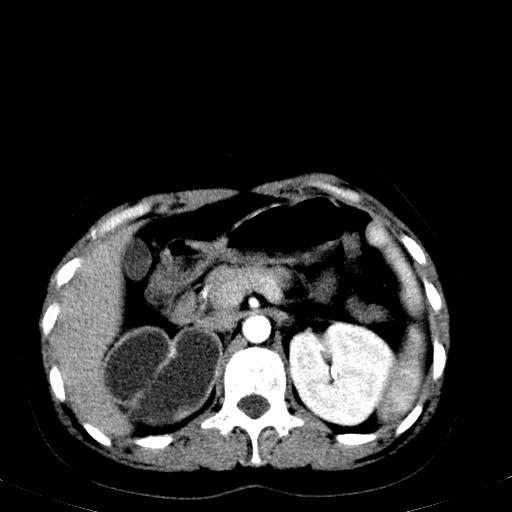

患者体检发现右肾体积增大,怀疑右肾积水

应该肾积水没有问题!

肾积水

右肾重度积水,以肾盏积水明显,有分隔,上段输尿管轻度扩张,管壁增厚,考虑肾结核可能,请结合尿检查,胸部拍片排除肺结核。

右侧肾积水、左侧肾结石 ,原因待查

患者尿常规正常,b超未发现明显结石,自身也无明显感觉异常。

请问多囊肾与肾积水怎么鉴别